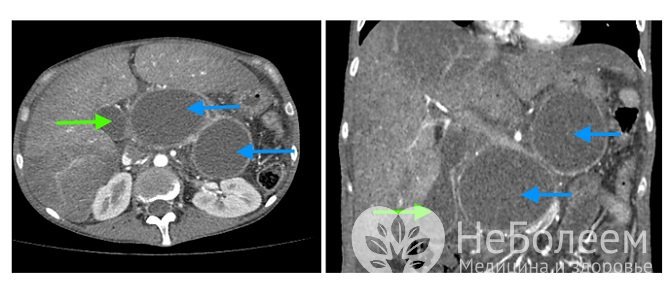

При обзорной рентгенографии органов брюшной полости выявляют оттеснение желудка, поперечной ободочной кишки кпереди и кверху или книзу от обычного положения. КТ и УЗИ помогают обнаружить четко ограниченное и заполненное жидкостью образование, связанное с поджелудочной железой.

Компьютерная томография - один из высокоточных методов, применяемых в диагностике панкреатических кистОсновным методом лечения является хирургический. Консервативная тактика применяется при незначительных (до 5-6 см) истинных кистозных образованиях с тонкими (до 1 мм) стенками и отсутствии выраженных клинических проявлений. В этом случае назначается диета, динамическое наблюдение под контролем УЗИ.